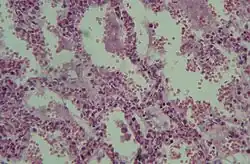

Histologie

Le SDRA est causé par une altération de la membrane alvéolocapillaire entraînant un syndrome lésionnel appelé « dommage alvéolaire diffus » entraînant une dysfonction sévère de l'oxygénation du sang et une hypoxémie sévère.

Le dommage alvéolaire diffus (DAD) comporte 3 stades[12] :

- Phase aigüe, exsudative : dépôt de membranes de fibrine le long des parois alvéolaires :

- infiltrat diffus neutrophilique avec hémorragie, destruction des pneumocytes I,

- œdème riche en protéines, fibrine + surfactant inactivé comblant les alvéoles pulmonaires,

- altération des pneumocytes II, diminution de la synthèse du surfactant pulmonaire,

- dure à peu près 6 jours ;

- Phase subaigüe, proliférative :

- hyperplasie, métaplasie des pneumocytes II,

- début d'organisation fibreuse,

- dure de 4 à 10 jours ;

- Phase chronique :

- réorganisation fibreuse interstitielle.